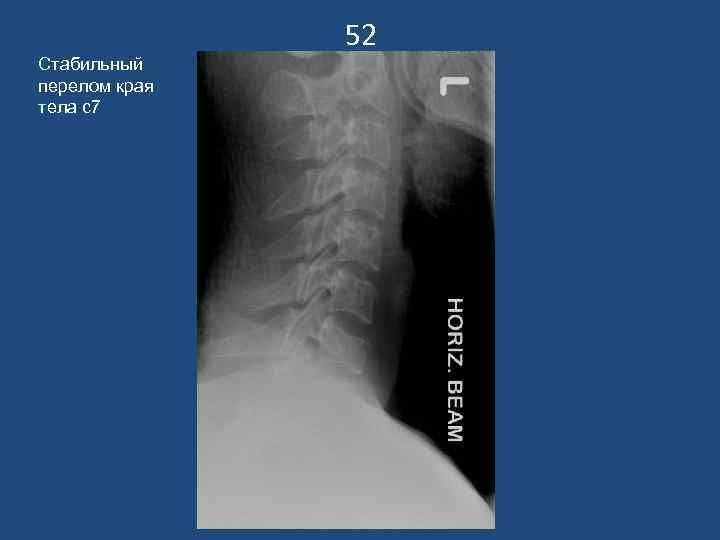

52 Стабильный перелом края тела с7